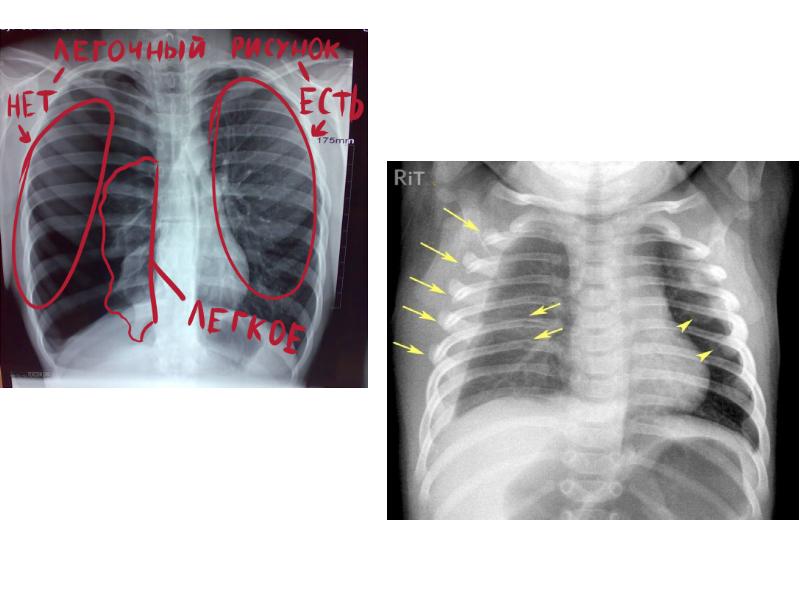

- 36. 6. Современные инструментальные методы исследования: рентгенография грудной клетки. Особенности рентгеноанатомии грудной